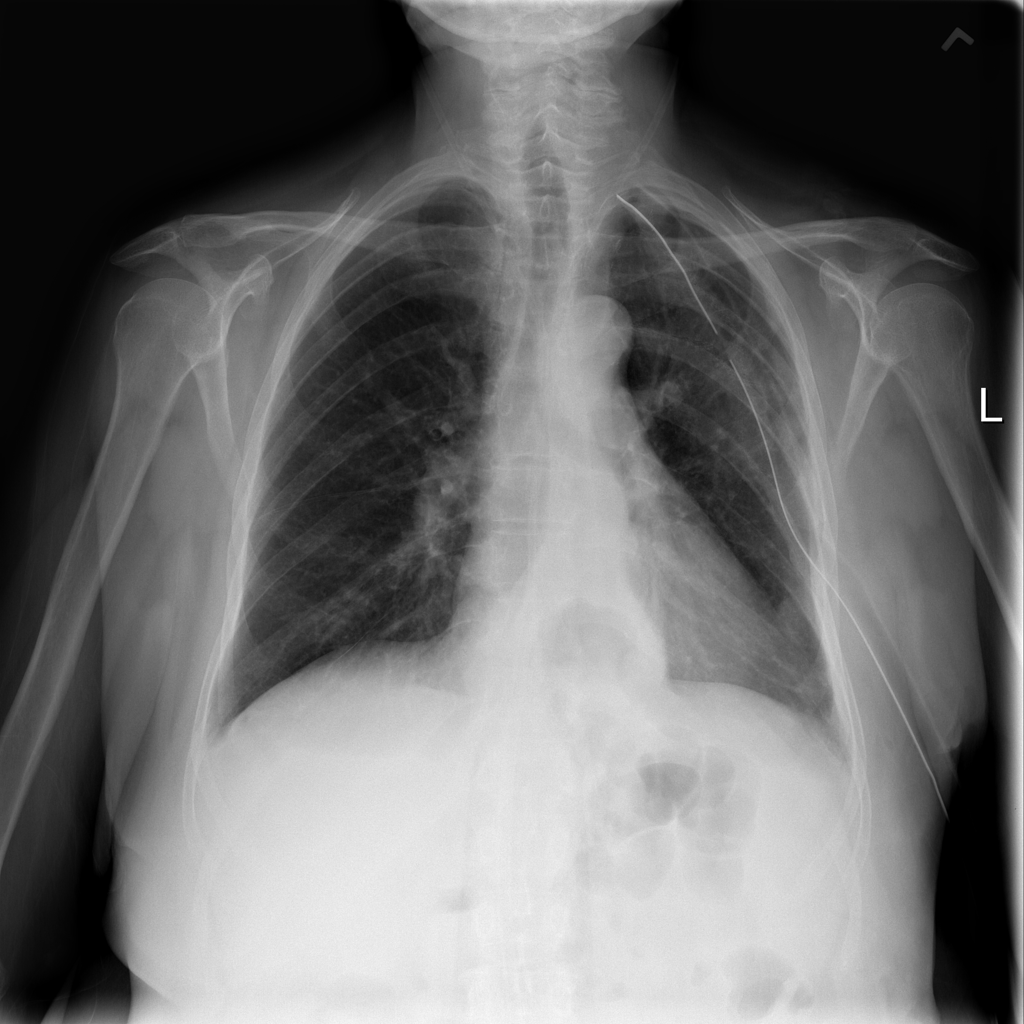

Showing up to 90 reference images for Hernia.

PAT-C048 · IMG-001Hernia

PAT-C048 · IMG-001

PA